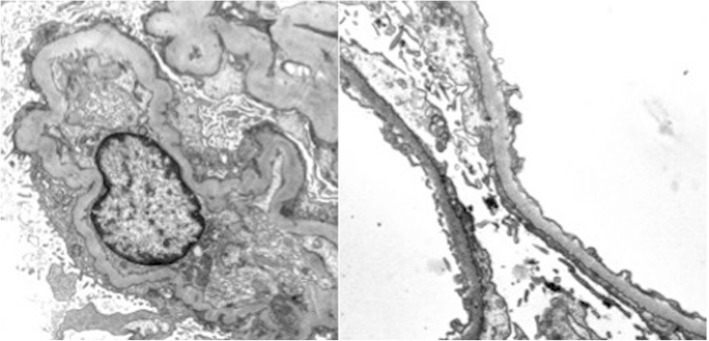

However, almost 2 years later, the patient developed severe acute-on-chronic renal failure with high-grade proteinuria resulting in generalized edema followed by secondary hyperparathyroidism and dialysis-dependent renal failure. Renal biopsy confirmed beginning anti-phospholipase A2 receptor antibody-positive membranous glomerulonephritis (MGN), a common cause of nephrotic syndrome (Fig. 2). One year of critical illness complicated by sepsis led to myasthenic crisis, but the patient recovered under repeated IVIg therapy and finally regained the partial ability to live autonomously.

Fig. 2.

Electron microscopy of the renal biopsy confirmed the diagnosis of membranous glomerulonephritis with few subepithelial osmiophilic deposits (courtesy of Prof. Kerstin Amann, Dept. of Nephropathology, University of Erlangen-Nürnberg)

MGN is one main cause of nephrotic syndrome and typically shows subepithelial immune complex and complement deposits of IgG and C3c in histological biopsies. The deposition is followed by complement activation causing sublytic damage presenting as proteinuria, hypertension, or microscopic hematuria.